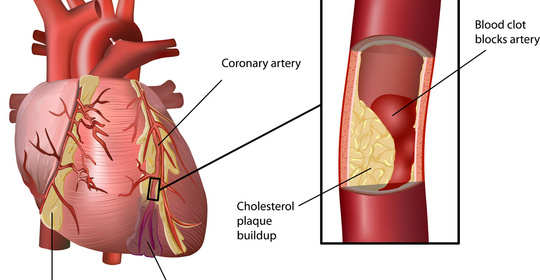

腦幹梗塞:前兆、原因、後遺症及治療方法

腦幹梗塞:診斷與治療

腔隙性腦梗塞:症狀、診斷與治療

腦幹梗塞:原因、症狀及治療方法

腦幹梗塞:症狀、恢復及預防